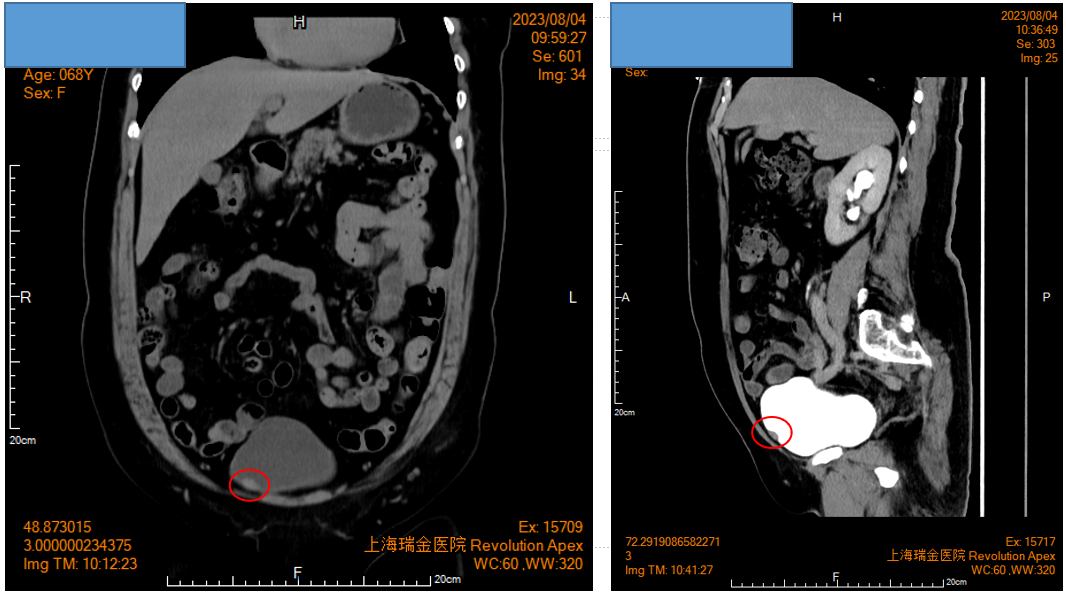

患者为一位68岁女性,因突发性右侧腰背部剧痛就诊。初步腹部CT平扫显示右侧输尿管结石伴随上段扩张及右肾积水。在症状缓解后进行的CTU检查中,意外发现膀胱前壁存在一处结节。

影像学检查提示:膀胱右前壁占位性病变

手术过程中,在膀胱右前壁观察到一个位于黏膜下的椭圆形肿物,基底较宽,尺寸约为1.5cm。